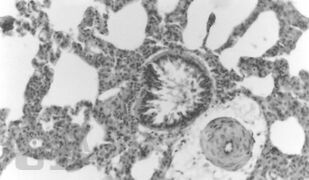

В учебно-методическом пособии приведены изменения микроциркуляции, дисциркуляторные и дистрофические изменения сердца, легких, диафрагмы и спинного мозга в раннем послеоперационном периоде на позвоночнике в эксперименте. Рекомендуется для врачей - ортопедов-травматологов, гистологов.